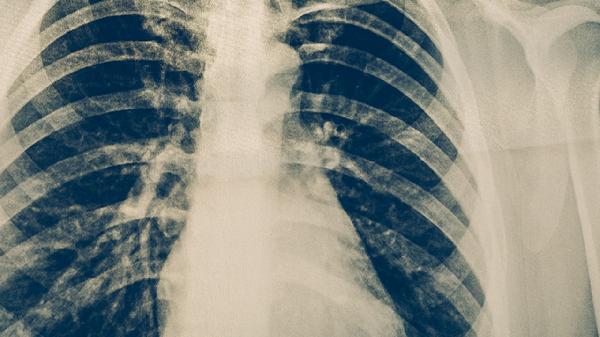

肺結(jié)核的初期癥狀主要有咳嗽、低熱、盜汗、乏力、食欲減退等。肺結(jié)核是由結(jié)核分枝桿菌感染引起的慢性傳染病,早期癥狀可能較輕微,容易被忽視。

肺結(jié)核患者應(yīng)注意保持規(guī)律作息,避免過(guò)度勞累,居住環(huán)境要定期通風(fēng)消毒。飲食上應(yīng)保證足夠的熱量和優(yōu)質(zhì)蛋白攝入,適當(dāng)補(bǔ)充維生素和礦物質(zhì)。治療期間嚴(yán)格遵醫(yī)囑用藥,不可擅自停藥或減量,定期復(fù)查胸部影像學(xué)和痰結(jié)核菌檢查。密切接觸者應(yīng)進(jìn)行結(jié)核菌素試驗(yàn)篩查,出現(xiàn)可疑癥狀及時(shí)就醫(yī)。保持良好的衛(wèi)生習(xí)慣,咳嗽、打噴嚏時(shí)遮掩口鼻,痰液要消毒處理,減少疾病傳播風(fēng)險(xiǎn)。